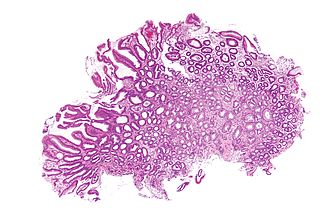

Reactive gastropathy. H&E stain.

LM foveolar hyperplasia - esp. tortuosity of glands in the "neck" region (S shaped glands), smooth muscle hyperplasia, scant inflammatory cells, +/-edema, +/-erosions

Features - triad:[5][1]

1. Foveolar hyperplasia.

• Tortuosity of glands in the "neck" region of the gastric glands.

• Associated with "mucin depletion" - cytoplasm not clear -- as is usual.

2. Smooth muscle fibre hyperplasia.

• Abundant eosinophilic lamina propria.

3. Scant acute & chronic inflammatory cells.